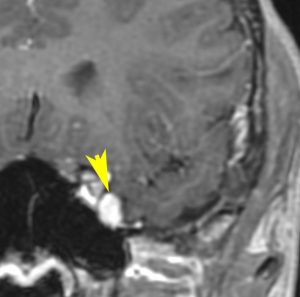

10才の時に,複雑部分発作(症候性てんかん)で発症しました。吐き気を感じた後に嘔吐して意識が遠くなる(意識減損)という症状であり,側頭葉てんかんです。脳波では左側頭葉に徐波律動がみられました。発作は頻回でしたがカルバマゼピンの投与で抑制されていましたが,MRIで腫瘍が発見されました。

左内側側頭葉グリオーマ mesial temporal glioma と呼ばれる腫瘍です。左の扁桃体,海馬鉤,海馬,海馬傍回に腫瘍が浸潤しています。T2強調画像とFLAIRでまだらな高信号で境界ははっきりしません。mass effectが少なく,増殖増大傾向のある腫瘍には見えないのが特徴です。下段右のように部分的にガドリニウム増強されるのも神経節細胞腫の特徴かもしれません。しかし,神経節膠腫,乏突起膠腫,乏突起星細胞腫(グレード2)なども疑われます。

手術中の脳波モニターでは,棘波が上側頭回の後方(ウェルニッケ領域)に存在し,深部電極刺入で海馬近傍にも棘波がみられましたが,もちろん上側頭回や海馬の切除はしませんでした。扁桃体 amygdala と海馬鈎 uncus の腫瘍部分のみを切除して手術を終了しています。海馬と海馬傍回には腫瘍を残しました。上のMRIは,その後6年経過した後のものですが腫瘍は全く同じ大きさです。抗てんかん薬も止めて,発作は全く生じていません。このような腫瘍は,扁桃体と海馬鉤を摘出することで,発作を完全に止めることができることがあります。ですから,最初の手術では,リスクのある余分な脳切除をしません。